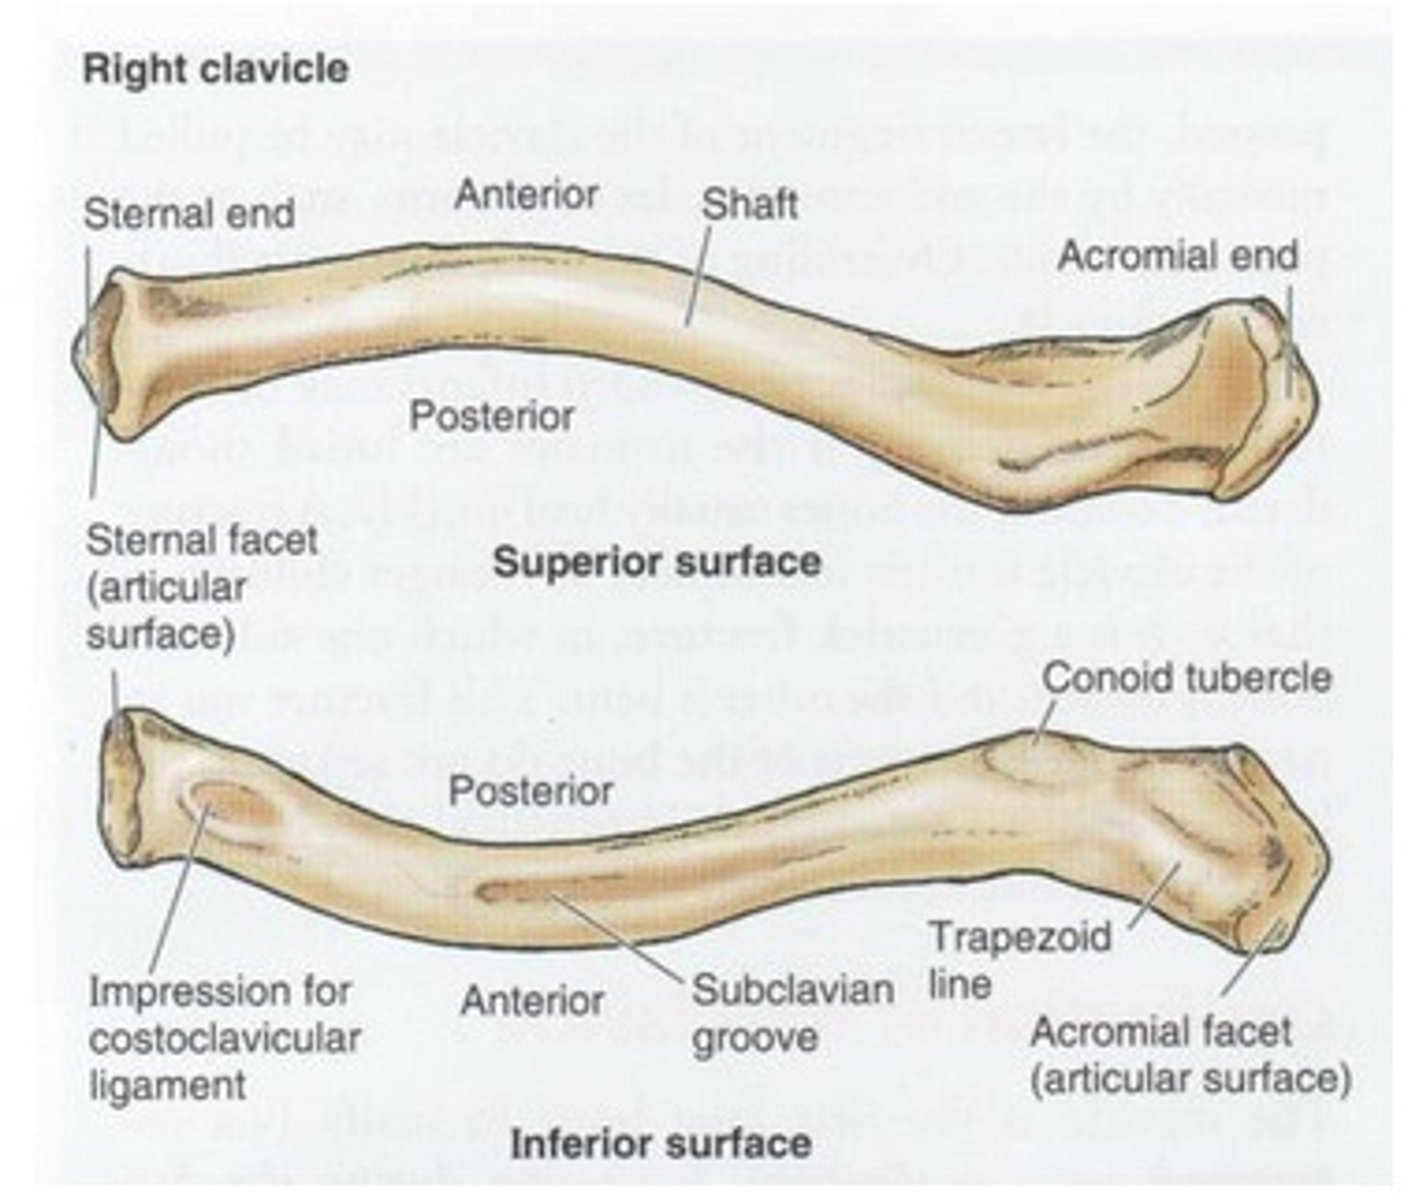

Parts of the clavicle:

- shaft

- superior surface

- inferior surface

Shaft of the clavicle:

double curved in the horizontal plane, which increases resilience

Middle half of the shaft of the clavicle:

convex anteriorly, and lateral half concave anteriorly

Sternal end of the shaft of the clavicle articulates:

articulates with manubrium via the sternoclavicular joint

Acromial end of the shaft of the clavicle articulates:

articulates with acromion via acromioclavicular joint

Location of superior surface of the clavicle:

lies deep to the platysma muscle and skin and it is smooth

Inferior surface of the clavicle:

rough surface with ligaments binding to it

Location of conoid tubercle of the inferior surface of the clavicle:

near acromial end of clavicle

Function of conoid tubercle on the inferior surface of the clavicle:

support for the medial part of the coracoclavicular ligament

Location of the trapezoid line of the inferior surface of the clavicle:

nearer to the acromial end than the conoid tubercle

Function of the trapezoid line of the inferior surface of the clavicle:

support for the lateral part of the coracoclavicular joint

Clinical relevance: fracture of the clavicle

Inflection point: The junction between the medial 2/3rd and lateral 1/3rd. The inflection point is the weakest point of the clavicle, more prone to fractures. The medial 2/3rd is going to be displaced superiorly by the action of the SCM (sternocleidomastoid) muscle